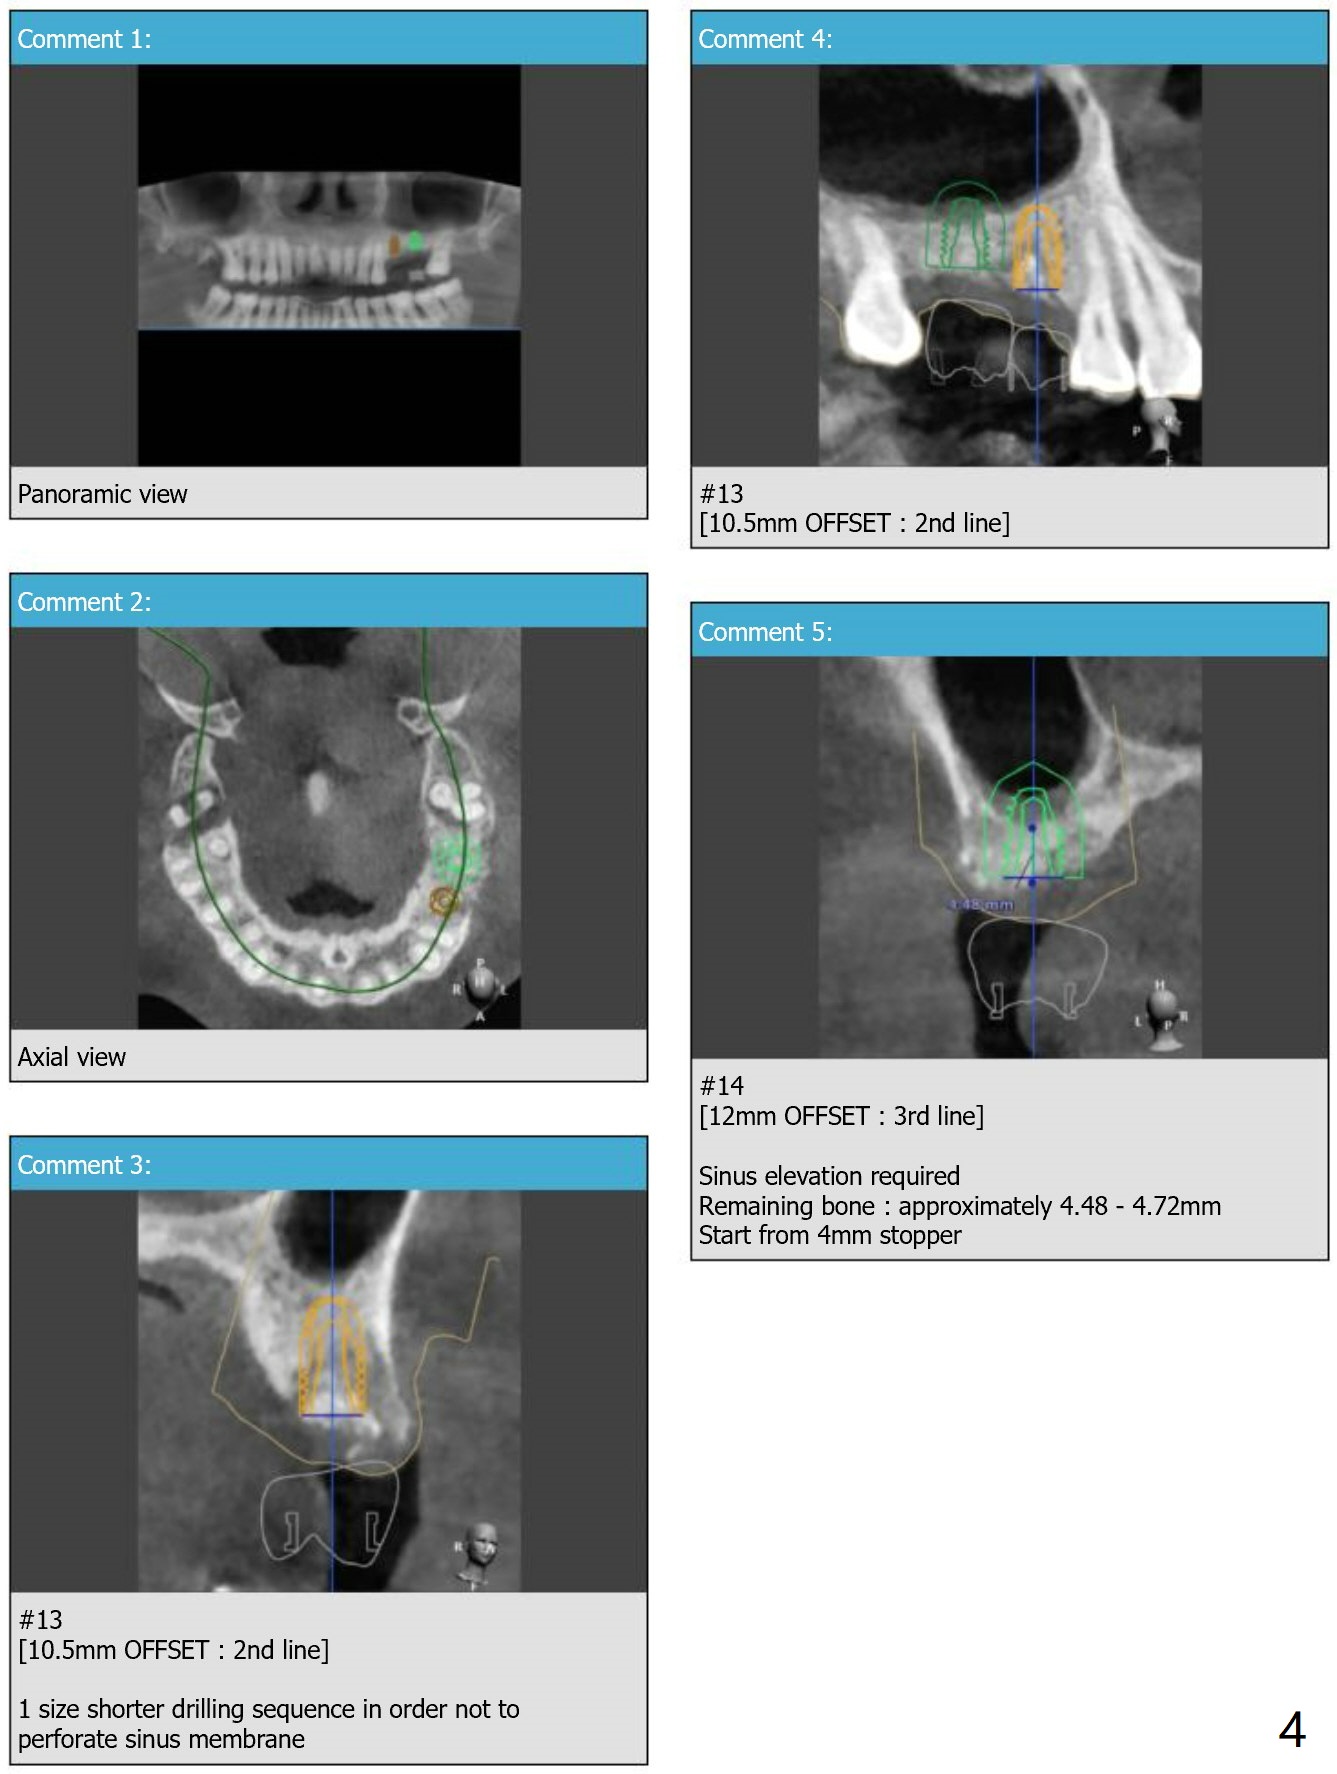

Short Implants with Sinus Lift at #14

Return to Upper Molar Immediate Implant, Armaments

Xin Wei, DDS, PhD, MS 1st edition 08/14/2018, last revision 08/30/2018